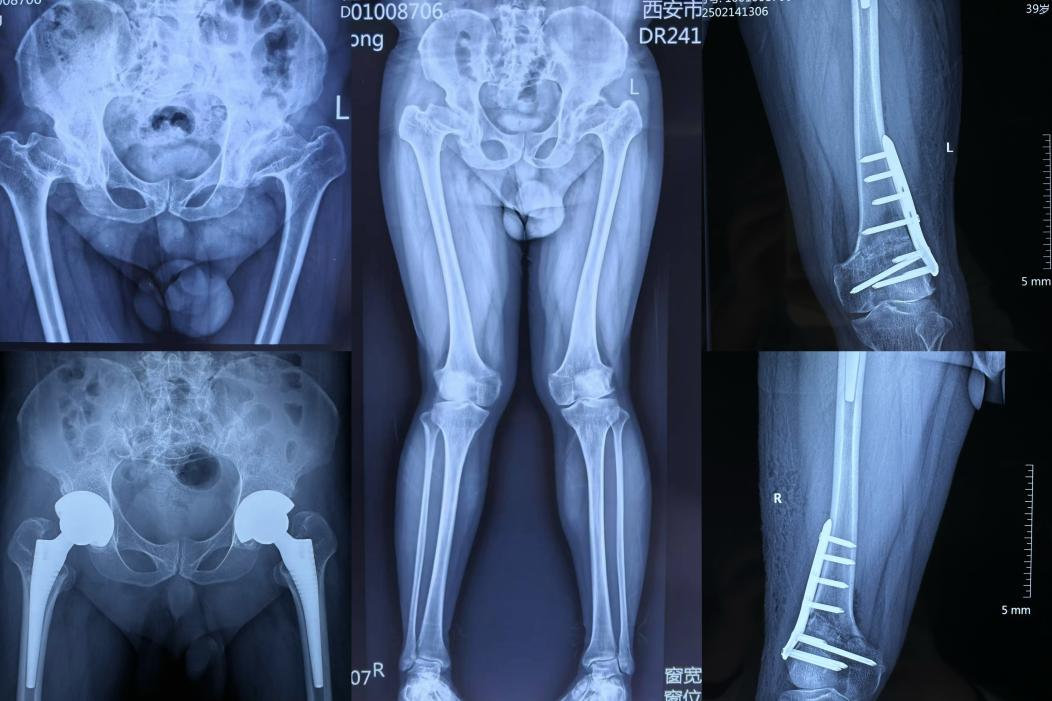

王先生今年39岁,患有多发性骨骺发育不良(Multiple Epiphyseal Dysplasia, MED),髋关节疼痛明显,同时伴有明显的膝外翻畸形(X形腿)。经过关节病院综合病区李辉主任团队接近三个小时的奋战,王先生手术顺利结束,当他麻醉苏醒看到自己直直的两条腿,激动的说“这是自己人生新的开始”。此次手术难度大、要求高,不仅突破DAA术式的传统禁忌症,更是让王先生通过“一个手术”而重拾自信。

王先生有明确家族史,结合病史、查体及影像学检查确诊MED无疑,其髋、膝关节均存在畸形,以髋关节疼痛为主。为了彻底解决王先生的病痛并且最大程度地减轻其身心及经济负担,避免多次手术,医疗团队精心规划一期全髋关节置换+膝外翻截骨矫形手术。由于王先生术前髋部畸形严重,虽然前入路(DAA)全髋置换手术难度大,但是能更少的损伤髋部软组织,术后体位无限制,他可以更便捷进行康复锻炼,尽早恢复关节功能。同时,通过股骨远端截骨手术,矫正膝外翻畸形,纠正下肢力线,既避免了关节早期退变,又明显改善了下肢外观。最终,通过一期全髋置换+截骨矫形手术,大大缩短王先生恢复周期,使他能更快地回归正常生活、工作,充分体现了医疗团队的技术和对患者全面关怀的人文理念。